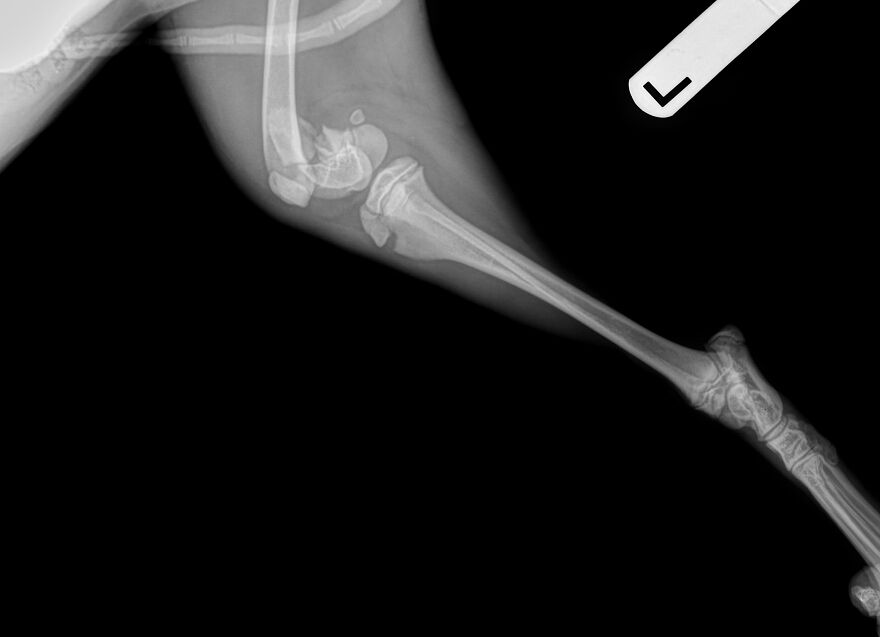

Her guardian, who describes Jazz as their best friend and constant companion, rushed her to the vet for x-rays and an emergency consult. The news was devastating, with results showing surgery is urgent, and the estimated cost is $4,000. Without the funds or eligibility for care credit, Jazz’s person faced an impossible choice.